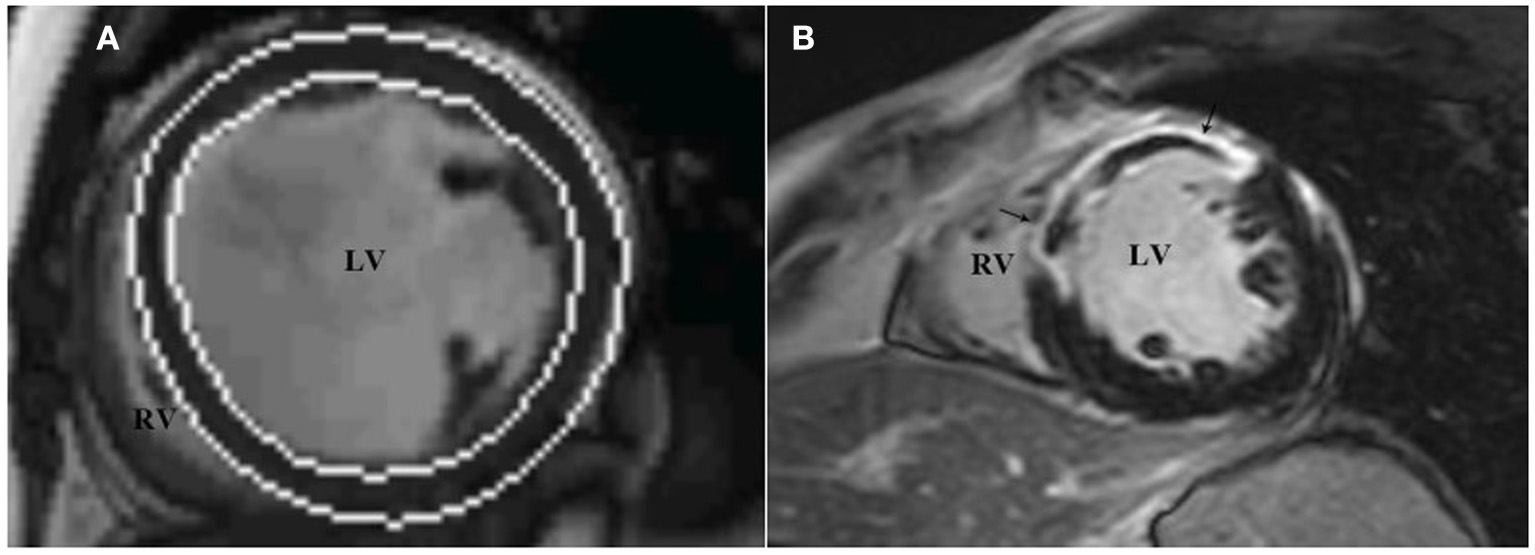

All images were reevaluated by two experienced observers, and all clinical data were blinded for analysis. By using Siemens Argus post-processing software (Argus software, Siemens Healthcare Erlangen, Germany), the left ventricular endocardium and epicardium were automatically tracked and contoured on the image (Figure 3A). The left ventricular cavity contained trabecular and papillary muscles. The recognition errors were corrected manually. Left ventricular end diastolic volume (LVEDV), left ventricular end systolic volume (LVESV) and left ventricular mass (LVM) were measured, and LVEF was calculated:

Figure 3

LV function and LGE analysis via cardiac magnetic resonance imaging. The analysis software automatically tracks the left ventricular endocardium and epicardium to measure left ventricular volume (A), and assesses the presence and distribution of left ventricular LGE through short-axis images (B), which show high signal intensity in the middle segment of the left ventricular septum, anterior wall. LGE, late gadolinium enhancement.

In accordance with the recommendation of the American Heart Association in 2002 (15), the left ventricular myocardium was divided into 17 segments, and the presence and distribution of LGE were evaluated using short-axis images. LGE (+) was defined as the myocardial signal at the LGE enhancement site higher than the 5SD threshold of the average signal intensity of the distal normal myocardium (Figure 3B). According to the CMRI data, the studied population was divided into two groups: patients without LGE (LGE-) and patients with LGE (LGE+).